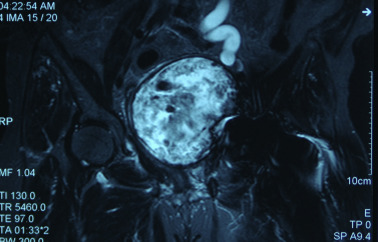

The patient was first considered for surgical decompression of the excretory system and relief of intraabdominal displacement, to be followed with a revision arthroplasty. The cystic sac containing a significant amount of debris material was aspirated and excised by the general surgeon. Fibrous wall of the cyst was continuous with the defect in the pelvic wall (Fig. 4 ). Decompression was successful and the patient was discharged because she denied a revision hip surgery. After 10 months, she referred to the hospital with recurrent symptoms of abdominal pain. The pseudotumor had reappeared in the same location, having the same size and compressive effect. This time a limiting pain was also present in the left hip joint. Hydronephrosis was relieved after insertion of double J catheter into the left ureter and the patient was referred to orthopedic department for revision of hip arthroplasty. During the revision surgery, following removal of loose acetabular component, the cystic lesion was visible through the acetabular defect and was aspirated. Acetabular defect was reconstructed using an acetabular reconstruction ring (Contour, Smith-Nephew, Memphis, TN, USA) supported with bone grafting and a cemented acetabular component was implanted. (Fig. 5 ) Femoral component was stable despite moderate osteolysis, thus only the femoral head was replaced. She was discharged after uneventful recovery.

AP radiograph after revision.